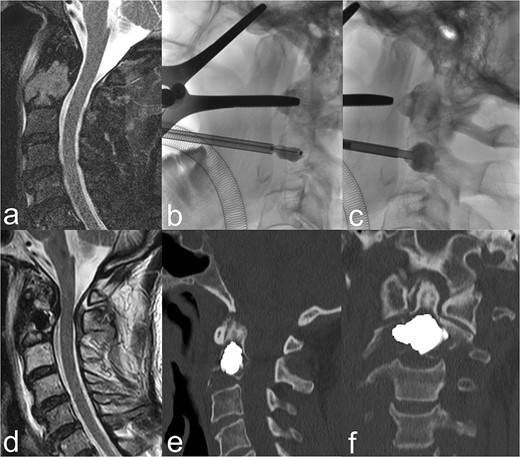

(a) The sagittal heavily T2-weighted fat-suppressed MRI imaging shows myeloma-related osseous destruction/pathological fracture of the corpus vertebrae axis. (b) BKP via a transoral approach. (c) After removal of the balloon catheter, the cavity created is filled with PMMA cement. (d) Centrally located cement plug in the sagittal T2-weighted MRI slice. (e) and (f) The sagittal and coronal reformed CT slices show a cement plug located centrally in the lesion. Cement leakage can be ruled out.

BKP was technically fully feasible. The control CT showed a central cement distribution in the tumour lesion, whilst cement leakage could be excluded (Fig. 1d–f). A significant, rapid and sustained pain reduction developed from 9 score points on the VAS pre-intervention to 2 points on postoperative day 2 and complete freedom from pain under provoked movement after 6 months (Fig. 2). The patient was able to be quickly remobilised after the intervention and be passed on for the further planned therapeutic measures. Patient satisfaction with the procedure was high, whilst quality of life improved significantly subjectively and objectively. The patient would not hesitate to have the intervention performed again.

Successful interventional treatment of osseous destruction of vertebral body C2, via a transoral approach, has only been reported by individual working groups to date. The first cement augmentations for the treatment of a symptomatic angioma [27], an aneurysmal bone cyst [28], a metastasis from a thyroid carcinoma [29], and a multiple myeloma [30] were performed without relevant complications using the vertebroplasty technique, whereby a marked reduction in pain was achieved clinically. Monterumici et al. [31] were the first to perform transoral kyphoplasty in vertebral body C2 in three patients with osteolysis, one of whom was a 69-year-old woman with MM, with no complications and marked clinical improvement in terms of sustained pain reduction and fracture stabilization. BKP is an osteoplastic procedure in which a preformed cavity is created in the osseous lesion by inflation of a balloon for cement insertion, whilst the circumference is compressed, thus minimizing cement leakage [21, 22]. CT diagnostic imaging also ruled out leakage in our patient, with good central cement filling (Fig. 1e and f). In this respect, the risk of cement leakage would appear to be more likely with the vertebroplasty procedure [32].